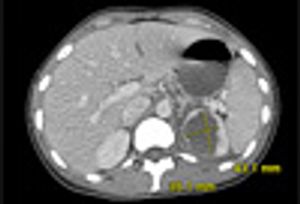

A 92-year-old woman presented with a 6-month history of progressively worsening fatigue, weight loss, generalized bone pain, and dyspnea on exertion. A skeletal survey found lytic lesions in the pelvis, sacrum, and calvarium (shown here).